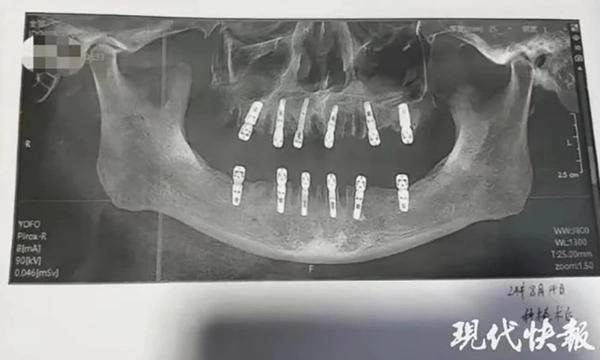

Người phụ nữ này đã đưa ra bằng chứng cho thấy cha cô đã nhổ 23 chiếc răng và cấy ghép 12 chiếc răng mới trong một lần, mà cô cho rằng đã gây ra cái chết sớm của ông 13 ngày sau đó.

Theo mẫu đơn đồng ý của bệnh nhân, cha của cô Shu thực tế đã nhổ 23 chiếc răng tự nhiên của mình trước khi khoan 12 lỗ vào hộp sọ và xương hàm để cấy ghép răng mới.

Tất cả những điều này được thực hiện trong một ngày, điều đó có nghĩa là ông phải chịu đựng nỗi đau không thể tưởng tượng được sau khi thuốc gây mê hết tác dụng.